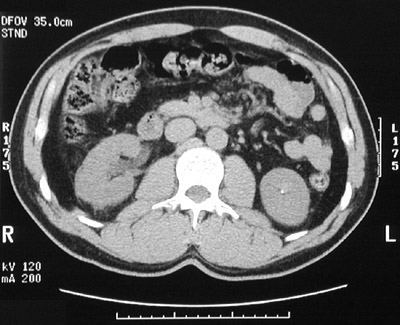

| These two abdominal CT scan views show a calyceal calculus within the left kidney. In the view below, a tiny calculus is seen in the region of the mid-right ureter. Straining the urine to catch the stone can be done so that the stone can be sent for chemical analysis. Determination of the cause for urinary tract calculi can help to provide treatment to prevent the calculi becoming a "renewable natural resource." |